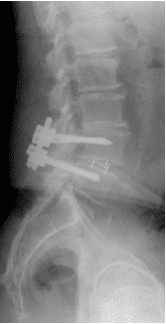

Patient underwent decompression laminectomy with decompression of nerve roots and transforaminal interbody fusion using PEEK (polyether ether ketone) cage and pedicle screw and rod fixation for fusion at L4-5 level.

Fusion was achieved in about 3 months and patient was asymptomatic.